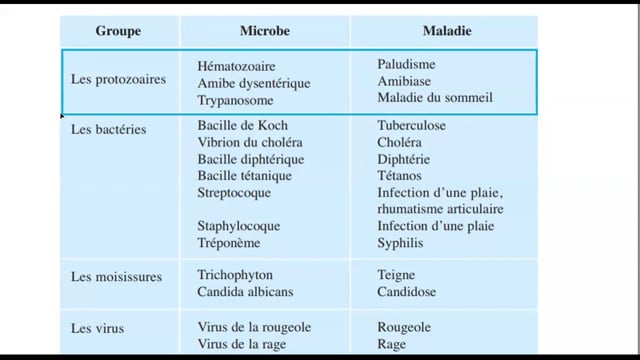

Sciences SVT

1ᴱ̀ᴿᴱ année

Enregistrement 2020-2021

Enregistrement 2021-2022

Enregistrement 2022-2023